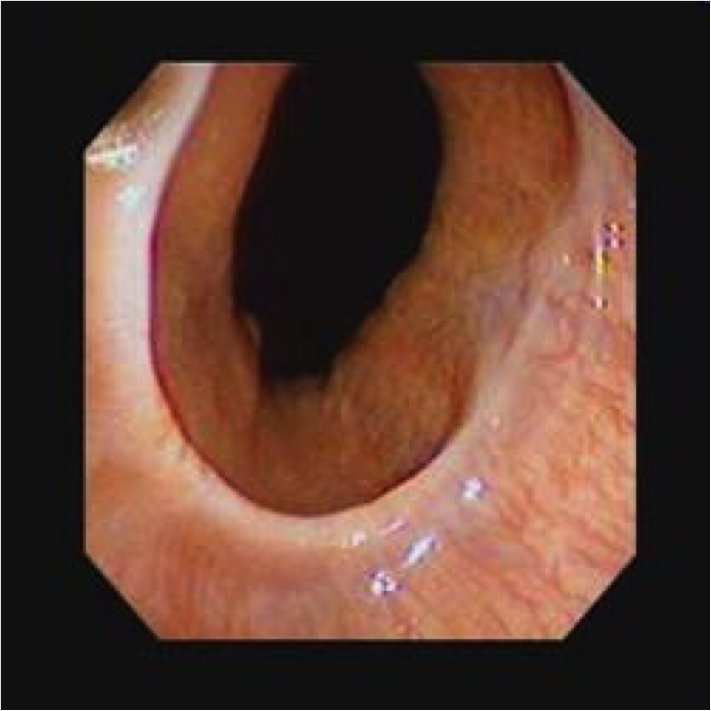

GERD

Hyperemia, vertical linear streaks represent superficial mucosal erosions/ulcers

GERD on bottom